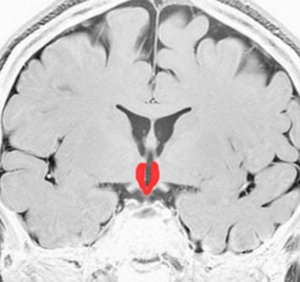

視床下部と下垂体の図です

赤く塗ってあるところが視床下部と下垂体です。ここには体の中にホルモンを分泌する働きの中枢があってとても大切な場所です。上の方が視床下部で,下に垂れ下がっているようなのが下垂体です。

赤く塗ったところが視床下部と下垂体です

視床下部は下垂体の上位中枢で,下垂体は視床下部の命令で機能しています